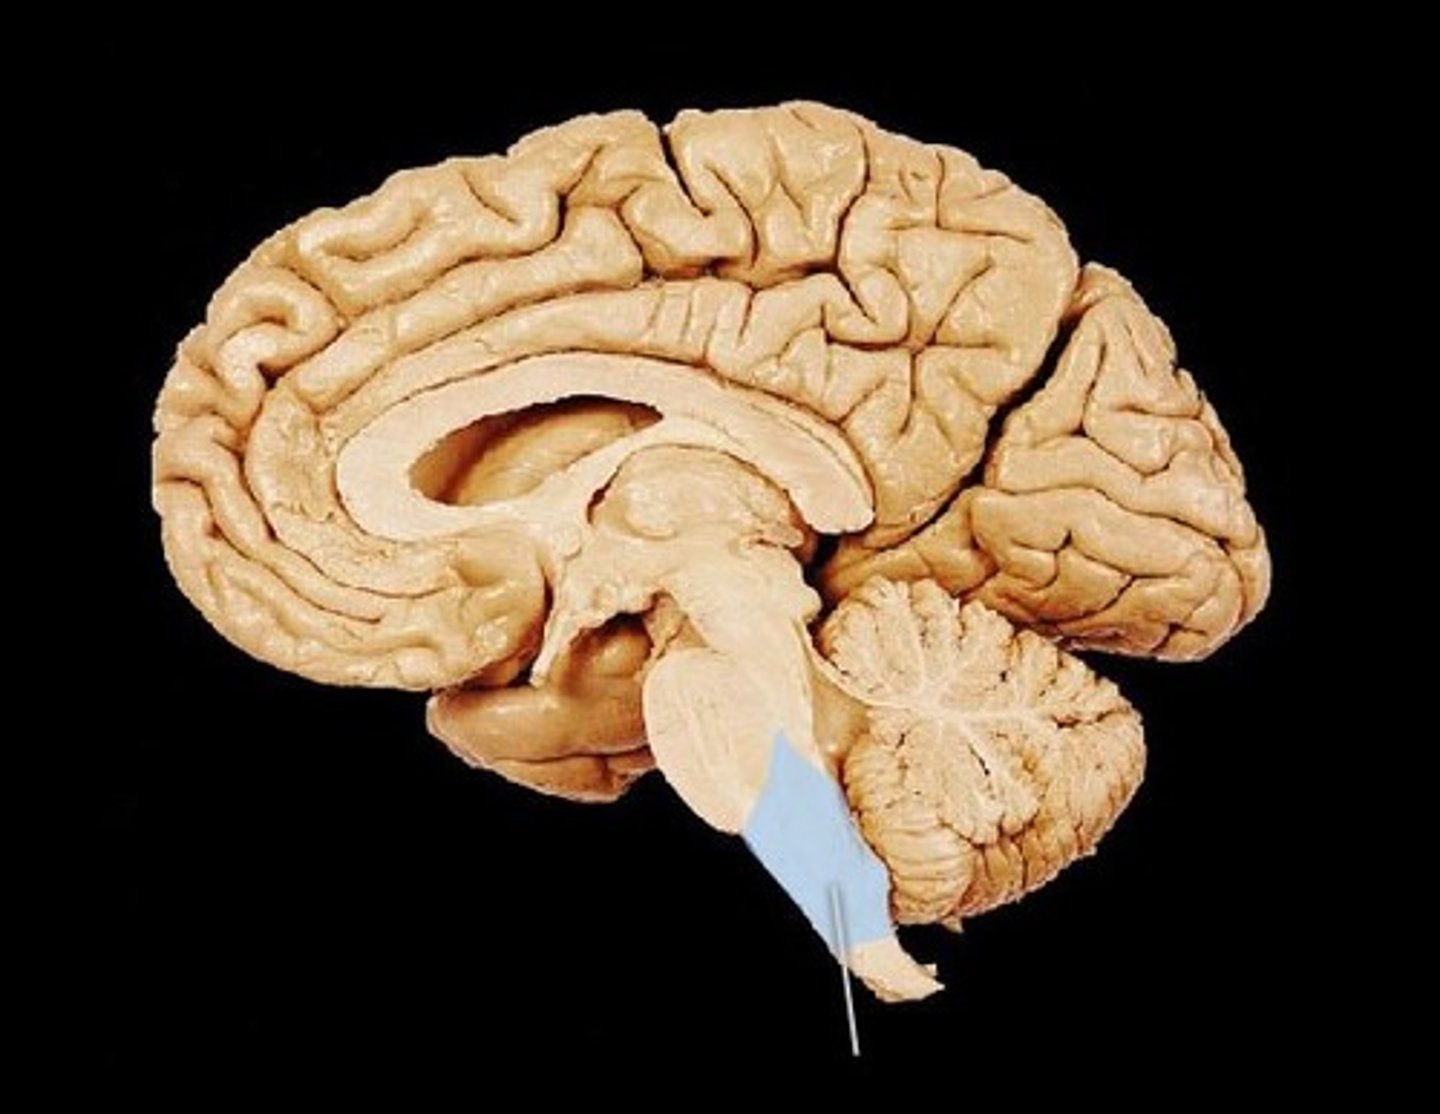

brainstem

the oldest part and central core of the brain, beginning where the spinal cord swells as it enters the skull; this is responsible for automatic survival functions; hindbrain

medulla

the base of the brainstem; regulates unconscious functions; breathing, circulation, heart rate

thalamus

the brain's sensory control center, located on top of the brainstem; it directs messages to the sensory receiving areas in the cortex and transmits replies to the cerebellum and medulla; handles all sense except smell

cerebellum

the "little brain" at the rear of the brainstem; functions include processing sensory input, coordinating muscle movement output and balance, and enabling nonverbal learning and memory.

limbic system

doughnut-shaped system of neural structures at the border of the brainstem and cerebrum; including the hippocampus, amygdala, and hypothalamus; located below the cerebral hemispheres; associated with emotions and drives.

a neural structure lying below (hypo) the thalamus; it directs several maintenance activities (eating drinking body temperature), helps govern the endocrine system via the pituitary gland, and is linked to emotion and reward.

Hippocampus

found in the Limbic System; handles learning and memory; specially the formation of NEW memories